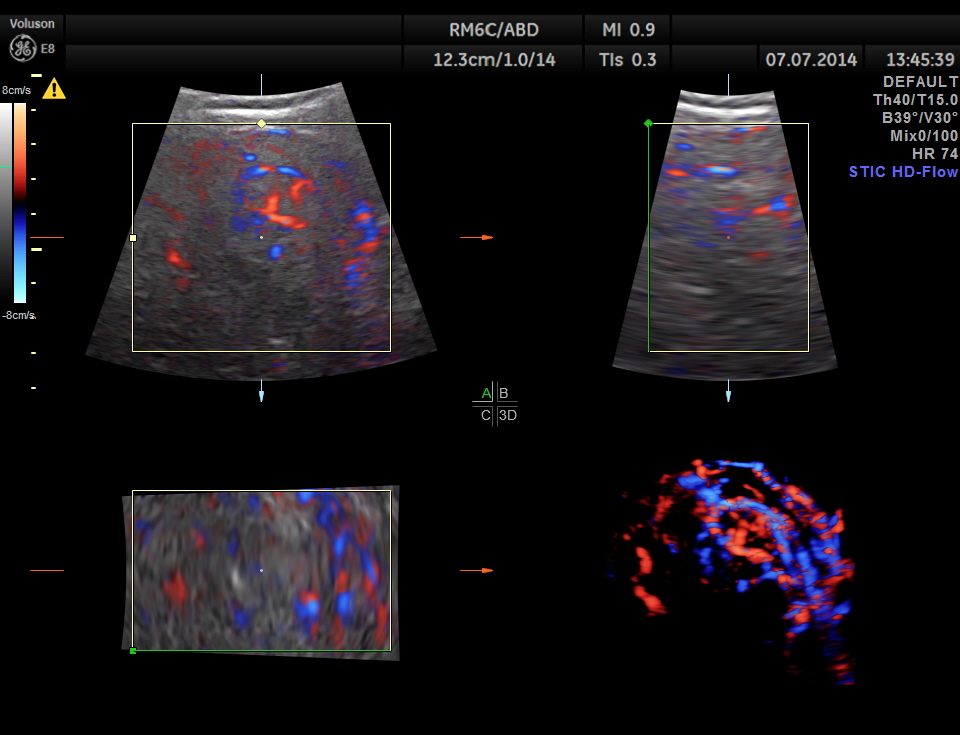

The mass shows increased vascularity on Power Doppler.